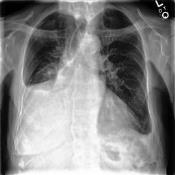

Large numbers of labeled medical images are essential for the accurate detection of anomalies, but manual annotation is labor-intensive and time-consuming. Self-supervised learning (SSL) is a training method to learn data-specific features without manual annotation. Several SSL-based models have been employed in medical image anomaly detection. These SSL methods effectively learn representations in several field-specific images, such as natural and industrial product images. However, owing to the requirement of medical expertise, typical SSL-based models are inefficient in medical image anomaly detection. We present an SSL-based model that enables anatomical structure-based unsupervised anomaly detection (UAD). The model employs the anatomy-aware pasting (AnatPaste) augmentation tool. AnatPaste employs a threshold-based lung segmentation pretext task to create anomalies in normal chest radiographs, which are used for model pretraining. These anomalies are similar to real anomalies and help the model recognize them. We evaluate our model on three opensource chest radiograph datasets. Our model exhibit area under curves (AUC) of 92.1%, 78.7%, and 81.9%, which are the highest among existing UAD models. This is the first SSL model to employ anatomical information as a pretext task. AnatPaste can be applied in various deep learning models and downstream tasks. It can be employed for other modalities by fixing appropriate segmentation. Our code is publicly available at: https://github.com/jun-sato/AnatPaste.

翻译:大量贴有标签的医学图像对于准确检测异常现象至关重要,但人工注解是劳动密集型和耗费时间的。自监学习(SSL)是一种培训方法,用于在不人工注解的情况下学习特定数据特征。一些基于SSL的模型被用于医学图像异常现象的检测。这些SSL方法有效地学习了多个特定领域图像的表解,如自然和工业产品图像。然而,由于医学专业知识的要求,基于SSL的典型模型在医学图像异常现象检测方面效率低下。我们展示了一个基于SSL的模型,可以进行基于解剖结构的、不受监督的异常现象检测(UAAD)。该模型使用解剖-觉粘贴(AnatPaste)增强工具。基于SSL的几种模型用于医学图像异常现象。这些异常现象与真正的异常相似,有助于模型识别这些异常现象。我们在三种开源的胸腔辐射数据集中可以使用模型,在基于解剖面结构结构的曲线下(AUSC),在92.1号中使用解析(Anal-SL)粘度图解为最高格式。